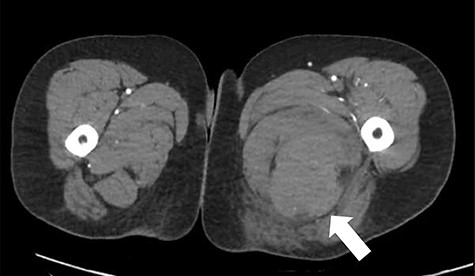

The patient was reviewed on ward around at 7:30 am by consultant orthopaedic surgeon. An urgent computed tomography (CT) angiography of the affected side was performed, as it was unclear if the haematoma was in the posterior or medial compartment; this demonstrated a large haematoma in the posterior compartment, with no cause identified (Fig. 1).

CT angiography axial slice demonstrating haematoma in posterior compartment of left thigh (white arrow).